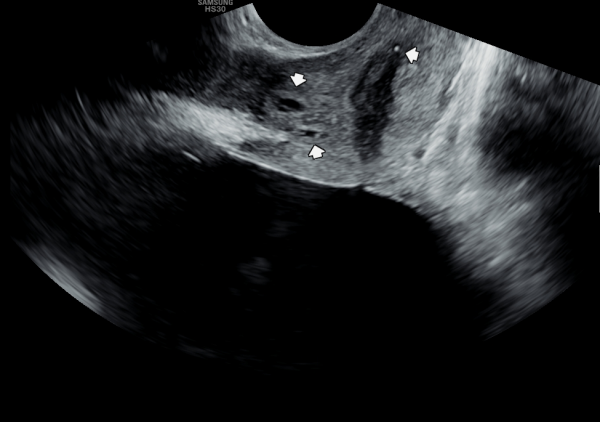

수년전부터 회음부 통증과 배뇨 장애로 내원 당일 검사한 경직장 전립선 초음파 검사상 사정관 입구의 미세 결석과

전립선의 낭종이 관찰되는 초음파 사진입니다.

A transrectal prostate ultrasound image taken on the day of the visit shows microcalcifications at the opening of the ejaculatory duct and cysts within the prostate, in a patient who had been experiencing perineal pain and voiding difficulties for several years.